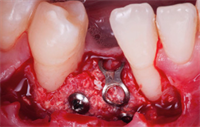

Guided Bone Regeneration is an important part of modern dental implantology and requires skills in application of the specific materials.  More importantly is knowledge needed about the behavior of various materials and indications for application in individual cases.

The majority of the materials used in the bone regeneration procedures have osteoconductive properties but with the help of natural growth factors we can improve their potential of healing with osteoinductive features.

Cases are presented and included are explanations of the biological principles which will help you better understand Guided Bone Regeneration.  At the end of this course, one will have a better understanding on how to incorporate GBR into one's dental practice.

Dr. Kris Chmielewski is a dentist with 20 years experience in implantology and Guided Bone Regeneration procedures. In his career he was using all available material types starting from autogenous bone, xenografts, synthetic materials and allografts. With excellent skills in photo documentation he is able to illustrate the surgical procedures and results of the treatment in the unique way.